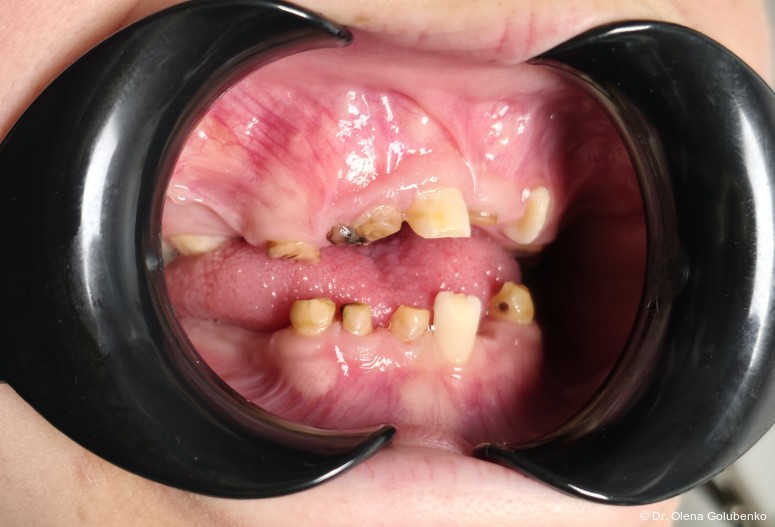

Der vorliegende Beitrag entstand aus einer kollegialen Anfrage: Eine 17-jährige Patientin mit ausgeprägten dentalen Auffälligkeiten wurde zur kieferorthopädischen Beratung überwiesen (Abb. 1a–c). Trotz zahlreicher vorangegangener zahnärztlicher Behandlungen war bis zu diesem Zeitpunkt keine syndromale Diagnose gestellt worden. Erst durch die sorgfältige Erhebung der allgemeinen und zahnmedizinischen Anamnese, die klinische Untersuchung sowie die gezielte Auswertung der dreidimensionalen Bildgebung ließ sich ein charakteristisches Muster erkennen. Auf dieser Grundlage ergab sich aus kieferorthopädischer Sicht der begründete Verdacht auf eine cleidokraniale Dysplasie, der die Vielzahl der dentalen, skelettalen und fazialen Befunde erstmals in einen schlüssigen klinischen Zusammenhang stellte.

Im vorliegenden Fall erfolgte die Überweisung durch eine zahnärztliche Kollegin mit der Bitte um kieferorthopädische Einschätzung des weiteren Vorgehens angesichts multipler nicht durchgebrochener Zähne, persistierender Milchzähne und zahlreicher überzähliger Zahnkeime.1

Das dentale Erscheinungsbild ist häufig sehr charakteristisch und erlaubt bereits früh einen Syndromverdacht. Typische Befunde sind:

• lang anhaltende Persistenz der Milchzähne

• ausgeprägte Retention der bleibenden Zähne

• multiple überzählige Zähne

• fehlende oder stark verzögerte spontane Zahndurchbrüche

• Engstände und Fehlstellungen